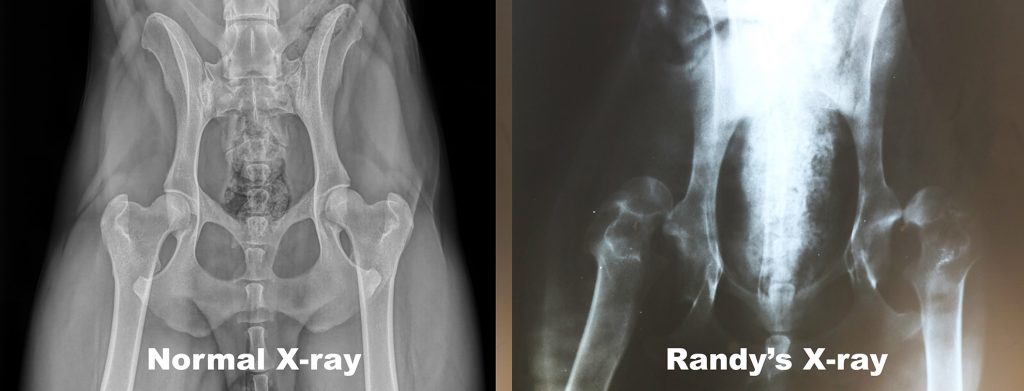

Yes, we will provide the surgery Randy needs to re-align his thigh bones and hip socket joints… both of them. The surgery on this “cheap puppy” will be about $3,200 for each hip. We’ll use the Cody Medical Fund to offset the cost. You can do two things to help Randy:

Randy’s operation will reposition his thigh bones to fit into the hip sockets correctly (noted with the colored bones).